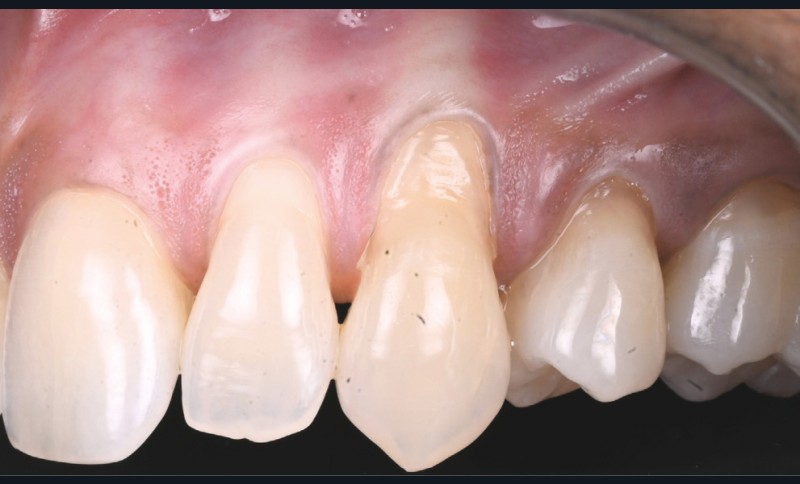

- secteur 2 : papille distale de 23 dodues et malposition de 24 (fig. 3) ➠ CAF (lambeau déplacé coronairement).